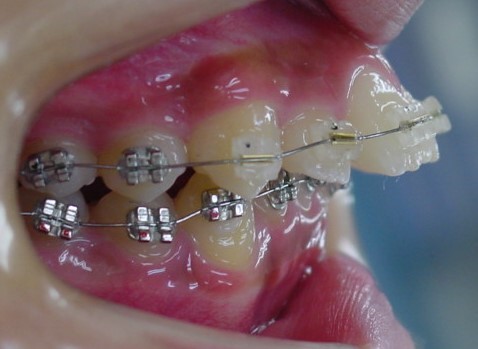

治療は上顎から矯正装置を装着していきます。

その後下顎の矯正装置を装着します。

この過程で歯並びが整いMEAW(マルチループ)を装着しやすくなります。

MEAW(マルチループ)を使用する事で上顎前突(出っ歯)や咬合高径(咬み合わせの高さ)の改善をしています。

☆治療途中

MEAW(マルチループ)を使用する事で上顎前突(出っ歯)や咬合高径(咬み合わせの高さ)を改善して2年6ヶ月で非抜歯での治療で綺麗な歯並びになりました。